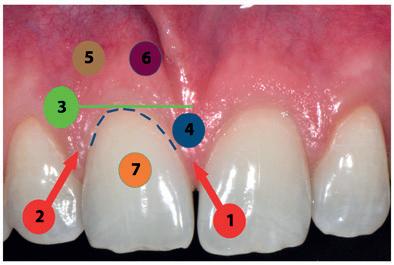

• Scoring pré-implantaire : méthode permettant de scorer chaque situation clinique pour rendre les résultats plus prévisibles.

• Définition du couloir esthétique osseux.

Situation avant la prise d’empreinte en sept. 2009

Situation pré-opératoire 09/2018 09/2018

Contrôle à 10 ans en septembre 2018.